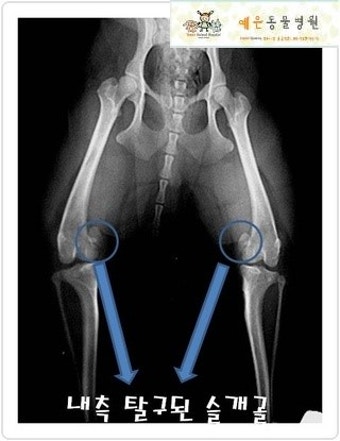

6. 검사와 진단 방법은?

병원에서는 촉진 검사로 먼저 확인하고, 필요하면 **X-ray(엑스레이)**를 찍어 확진합니다.

심한 경우 MRI 검사가 필요한 경우도 있지만, 대부분 물리적 검사로 충분히 확인 가능해요.